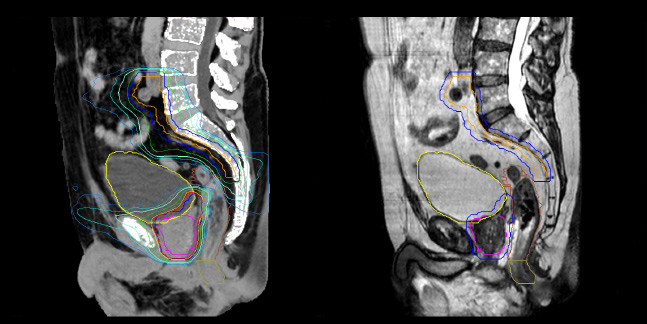

Evaluation of MRCAT dosimetric accuracy

Dosimetric equivalence validation was performed on 43 patient cases by comparing MRCAT-based dose plans overlaid on CBCT image dataset and on the corresponding MRCAT image dataset. Mr. Bolard and Dr. Champion found good agreement between MRCAT-based and CT-based dose calculations, with a mean dose ratio of 1.007 (0.991-1.014). The 3D gamma score was greater than 95% (95.2-99.0%) for all plans checked. A poster on this work was accepted for presentation at ESTRO 2020.

Dose plans overlaid on CBCT image dataset (left) and on MRCAT image dataset (right).